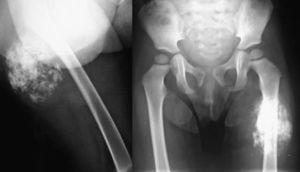

En la radiografía simple a las 2-6 semanas se aprecia una calcificación tenue, a partir de las 6 semanas aparece una masa circunscrita con calcificación periférica. Característicamente, tiene un anillo periférico calcificado y centro radiotransparente, a diferencia del osteosarcoma paraostal, que presenta una calcificación central y periferia radiotransparente2, 3, 4.

El diagnóstico definitivo es mediante biopsia, que descarta la malignidad del proceso1, 2, 3, 4. En esta paciente, tras la confirmación anatomopatológica, se realizó la exéresis quirúrgica de la tumoración.